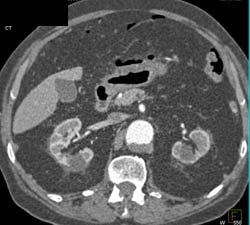

Diagnosis

Antral Pseudomass